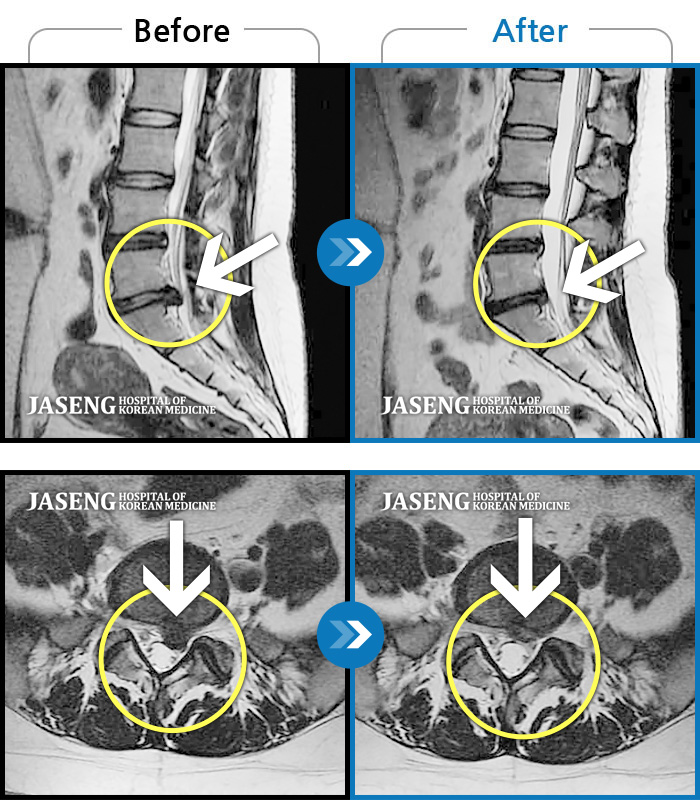

Before

After

환자에게 사전 동의를 받아 동일 조건에서 촬영되었습니다.

개인에 따라 치료 후 부작용이 발생할 수 있으니 의료진과 상담 후 치료를 진행하시기 바랍니다.

허리 숙일 때, 앉을 때, 보행시 허리 통증 증가, 좌측 발목~무릎부위 통증